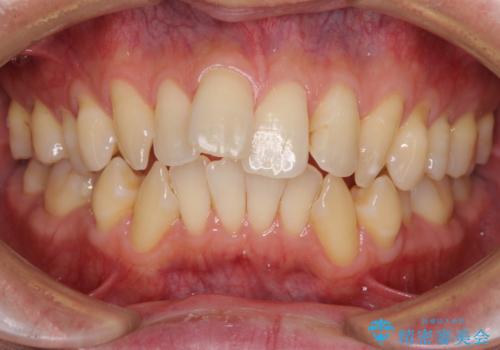

出っ歯を改善した後に真っ白な歯に 矯正歯科治療と審美歯科治療